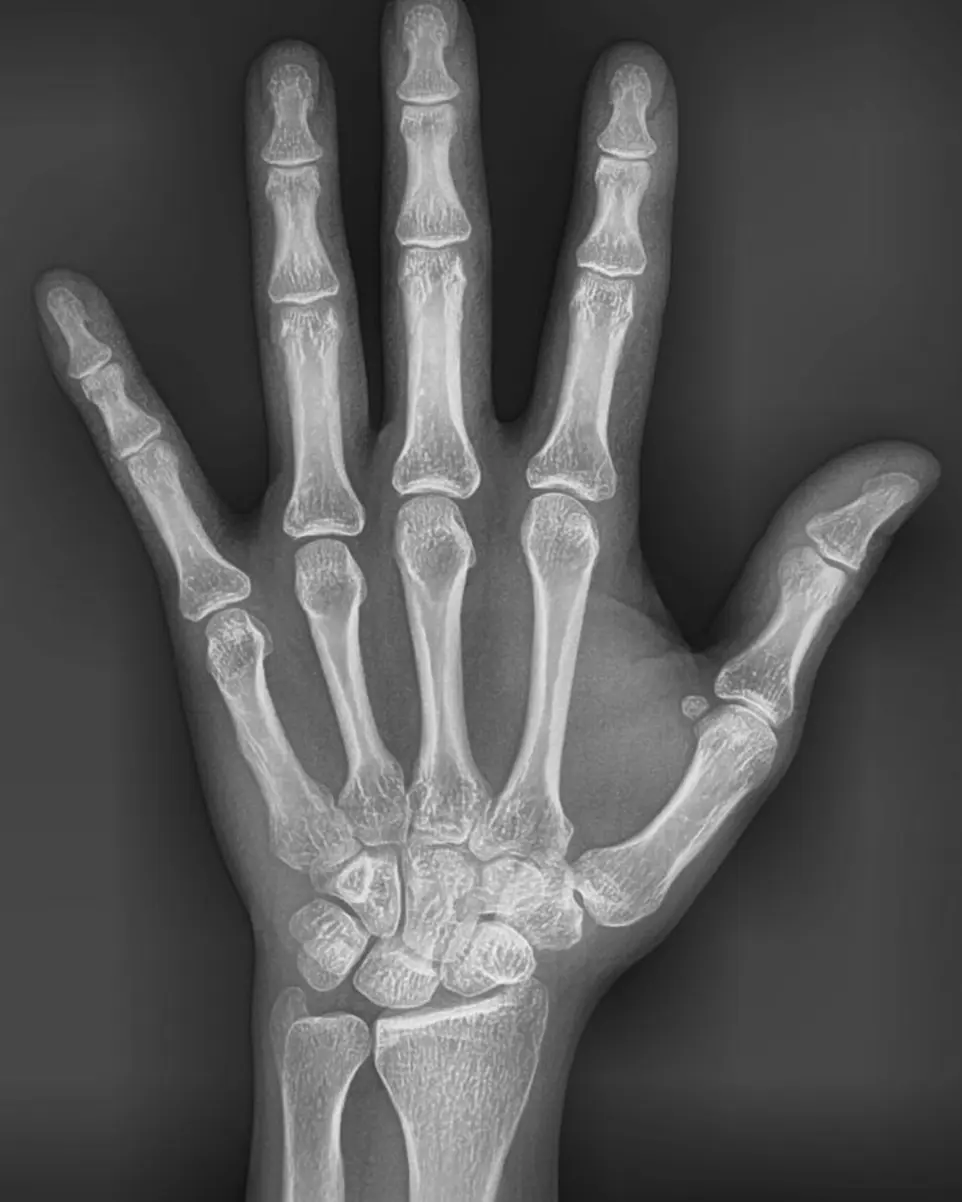

• Radiografía Carpal: Para analizar el crecimiento óseo en niños y adolescentes a través de la muñeca.

Radiografía Carpal